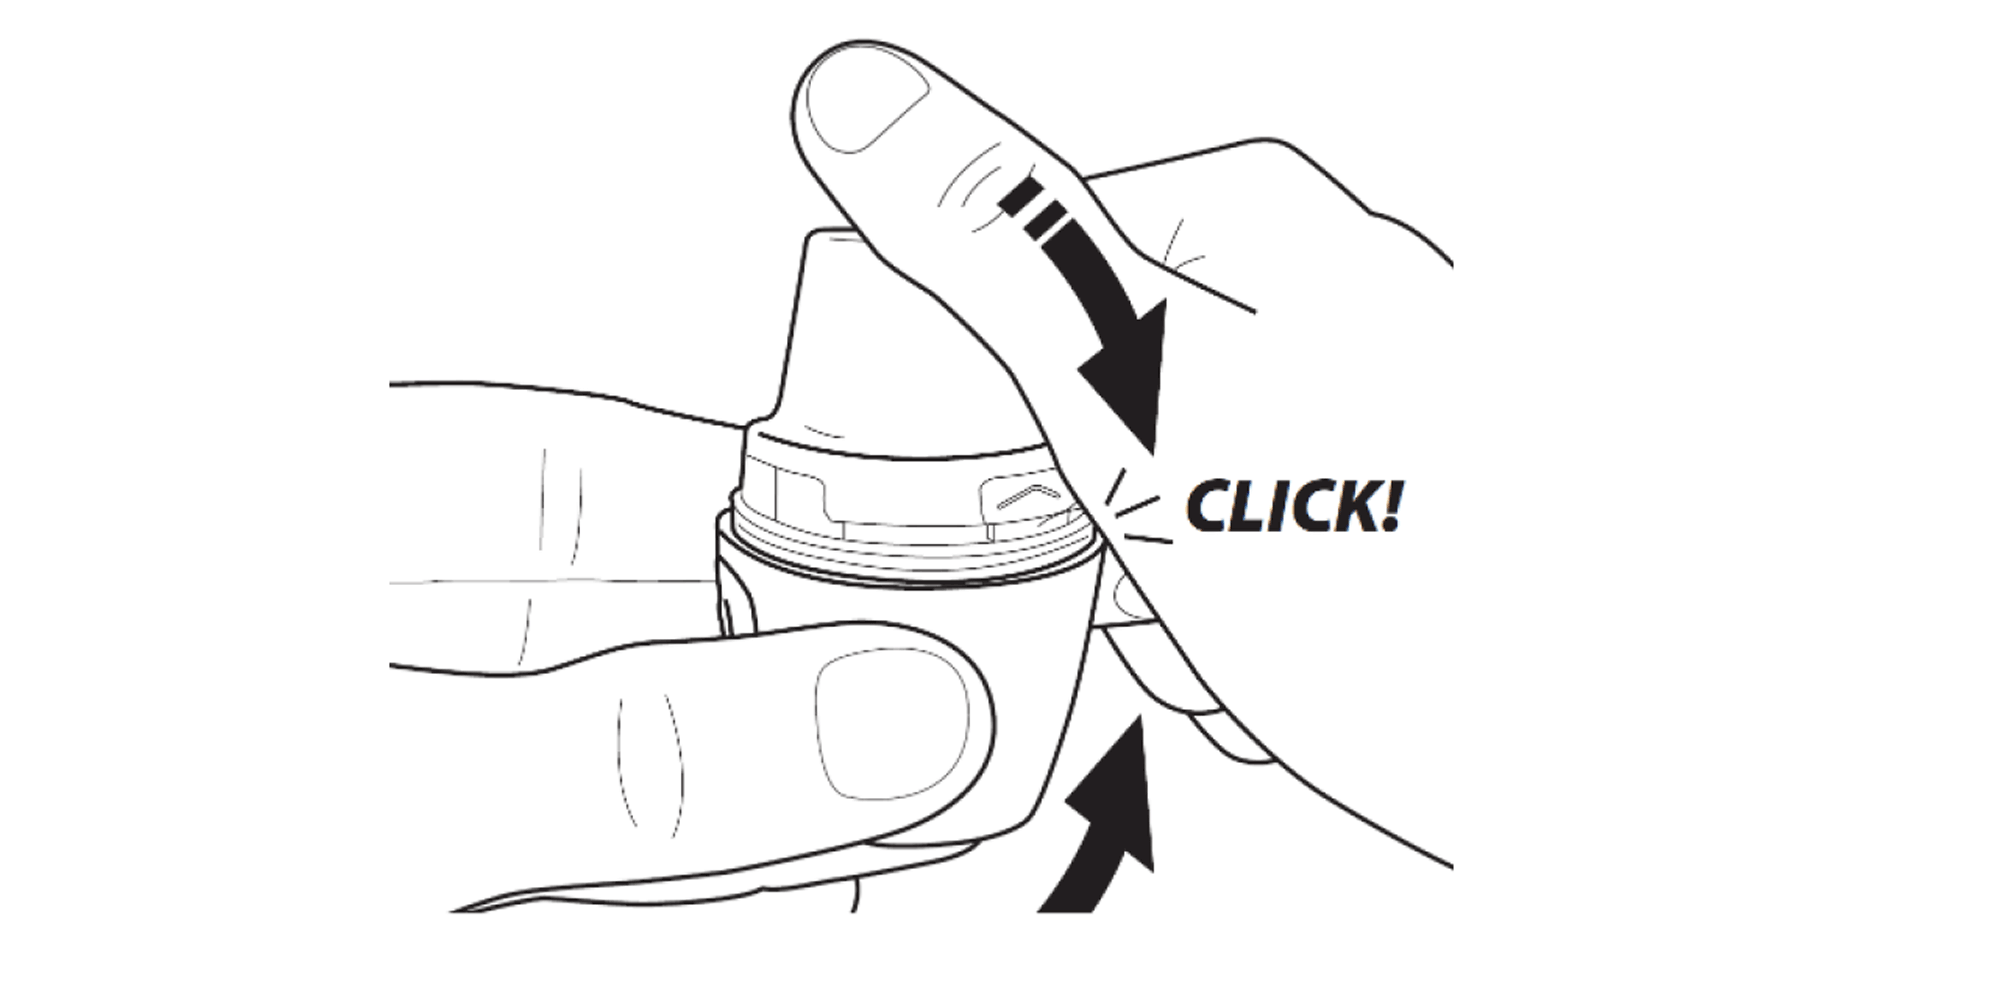

Firmly press the mouthpiece closed until you hear a click.